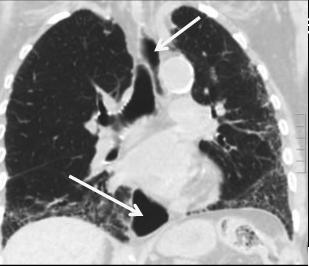

chaussette . Image TDM en fenetre parenchymateuse pulmonaire

,se donne des images si net de oesophage en coupe axiale ,

sagitale et de frontale ( voie image )

Mega oesophage : image radiologique

TDM fenetre parenchymateuse en coupe axiale |

Image Achalasia de oesophage en

coupe TDM sagitale |

Meme cas en coupe TDM frontale ( coronale

) . |